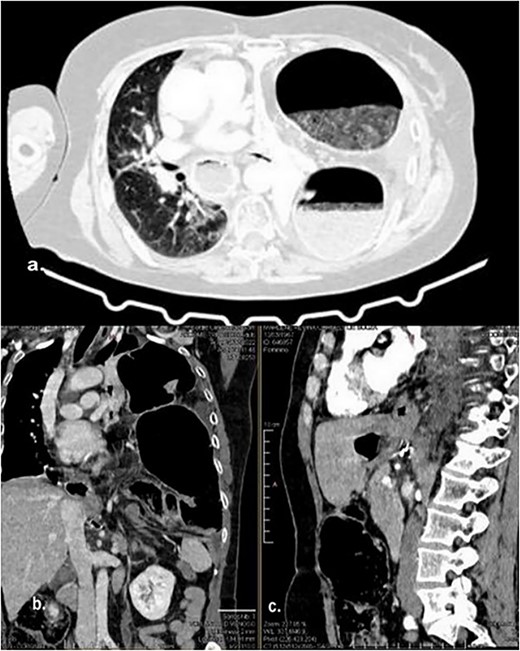

The abdominal computed tomography (CT) scan exhibited signs of esophagectomy with gastric lifting, a type IV hiatal hernia and colon herniation into the thorax (Fig. 1a and b). This was full of feces and symptoms of volvulus in the involved segment, with no free liquid in the cavity. Laboratory testing revealed an elevated protein C-reactive of 77, with normal white blood cells. Renal function and electrolytes were within normal limits.

Different sections of the CT study demonstrate the mediastinal position of the transversal volvulus. (a) Axial CT section of the abdomen showing signs of esophagectomy with gastric lifting, a type IV hiatal hernia and colon herniation into the thorax. (b) The coronal CT section of colon herniation into the thorax. (c) The sagittal CT section of the thorax and the abdomen shows the posterior mediastinal position of the colon herniation into the thorax.